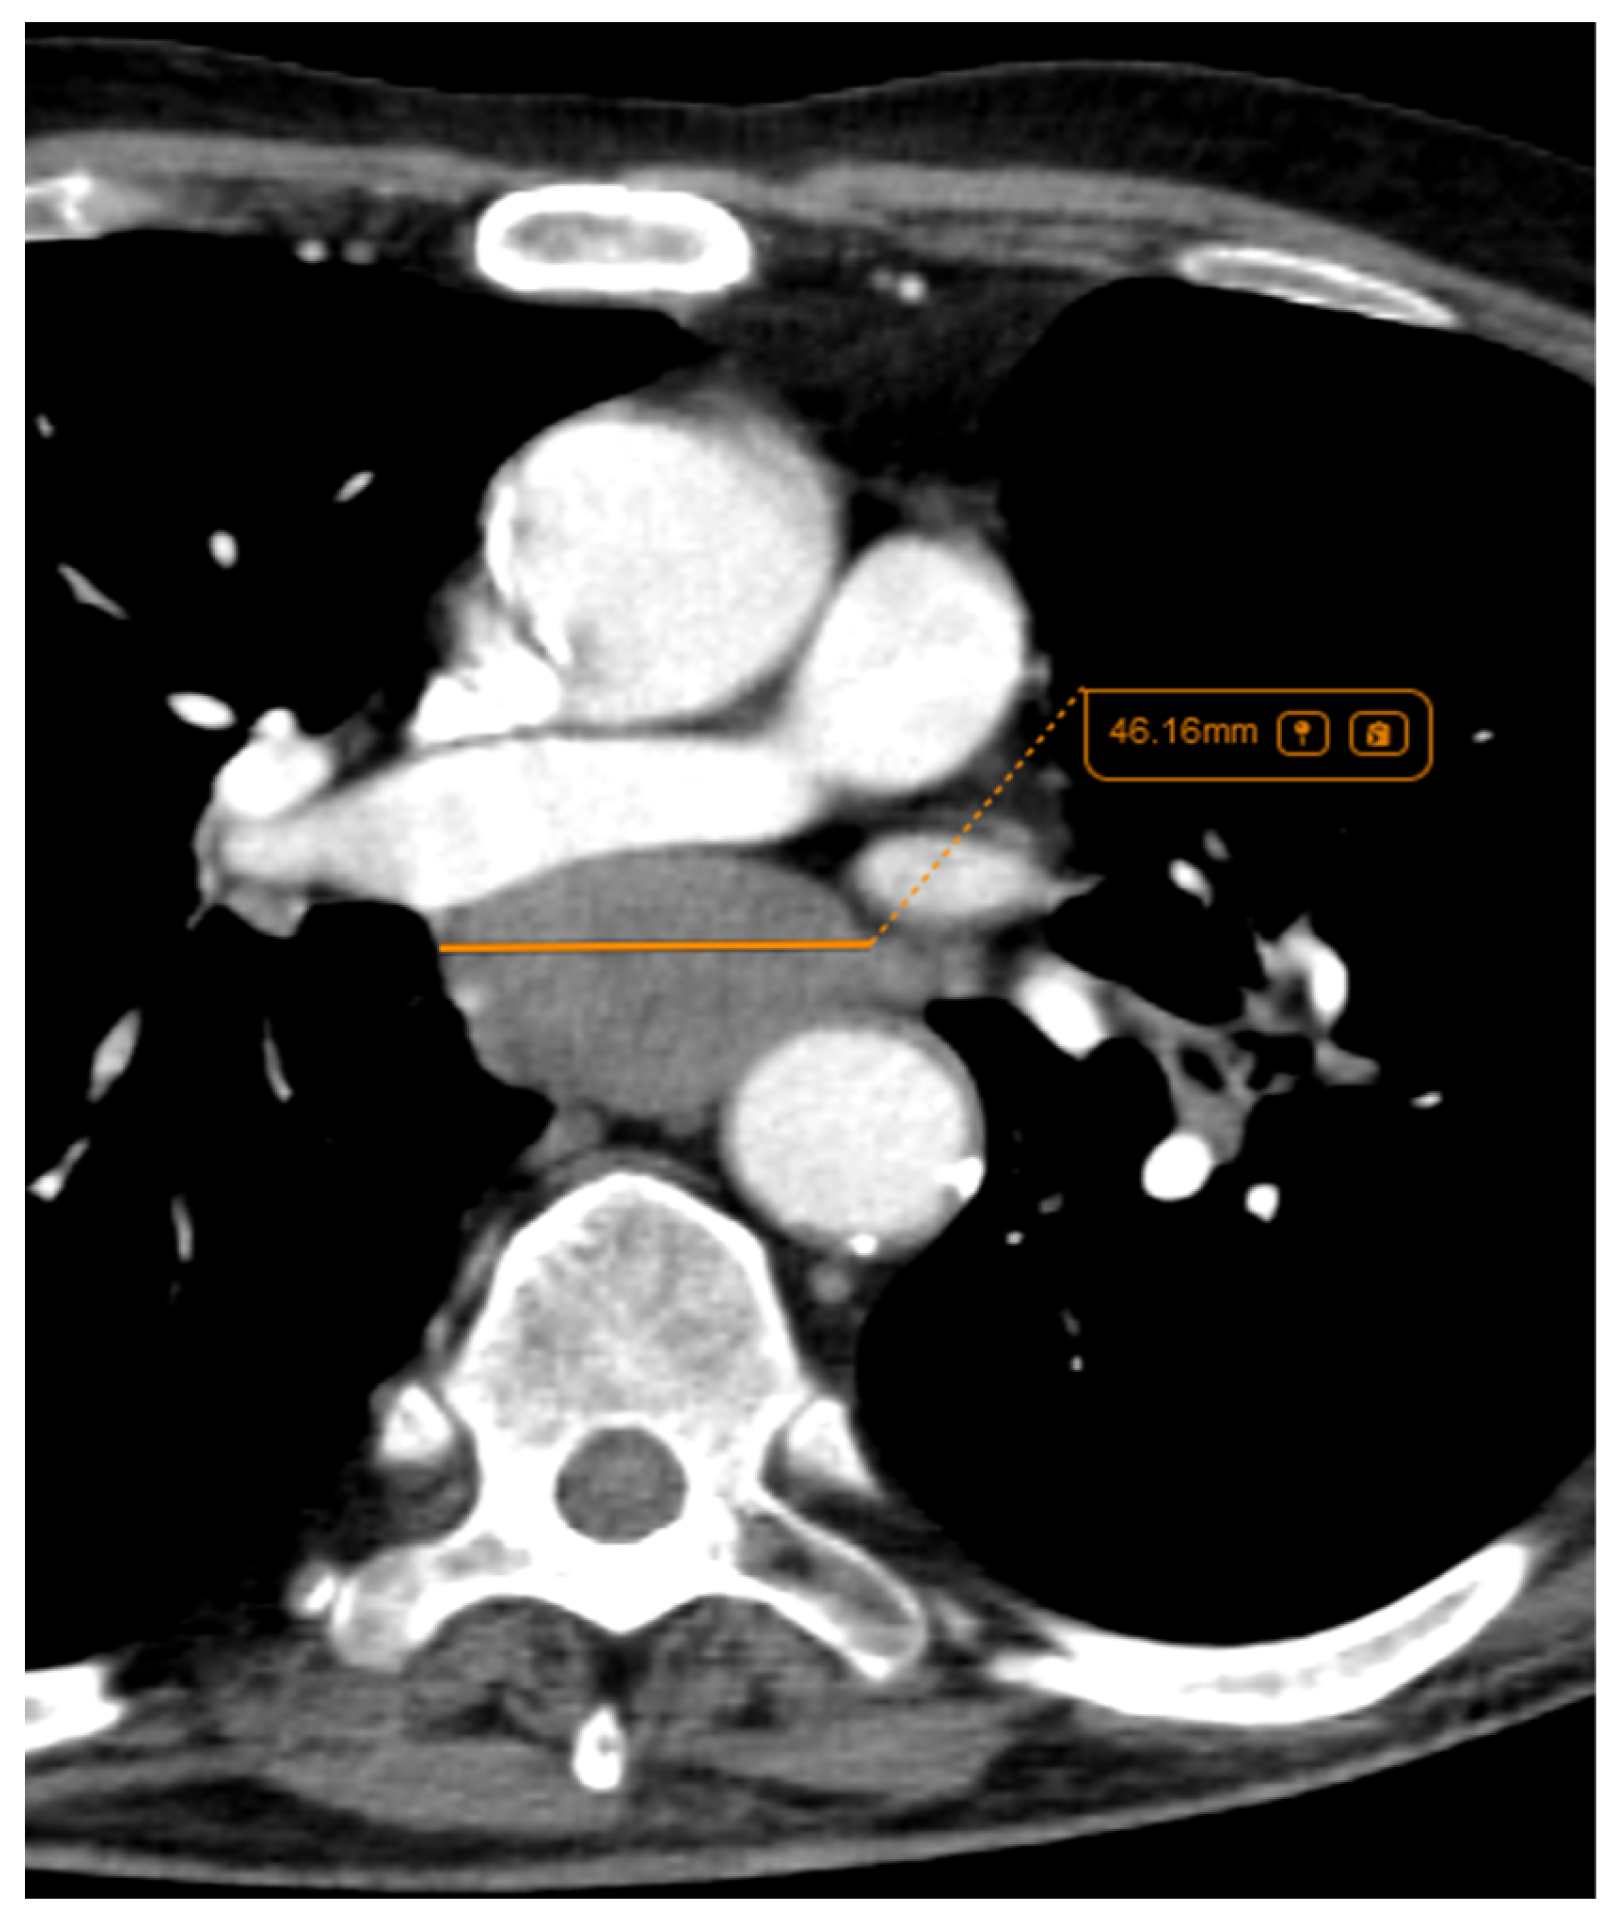

3.2.5. Local Invasion

3.2.6. Other Features—Bronchial Obstruction and Vascular Bundle Thickening